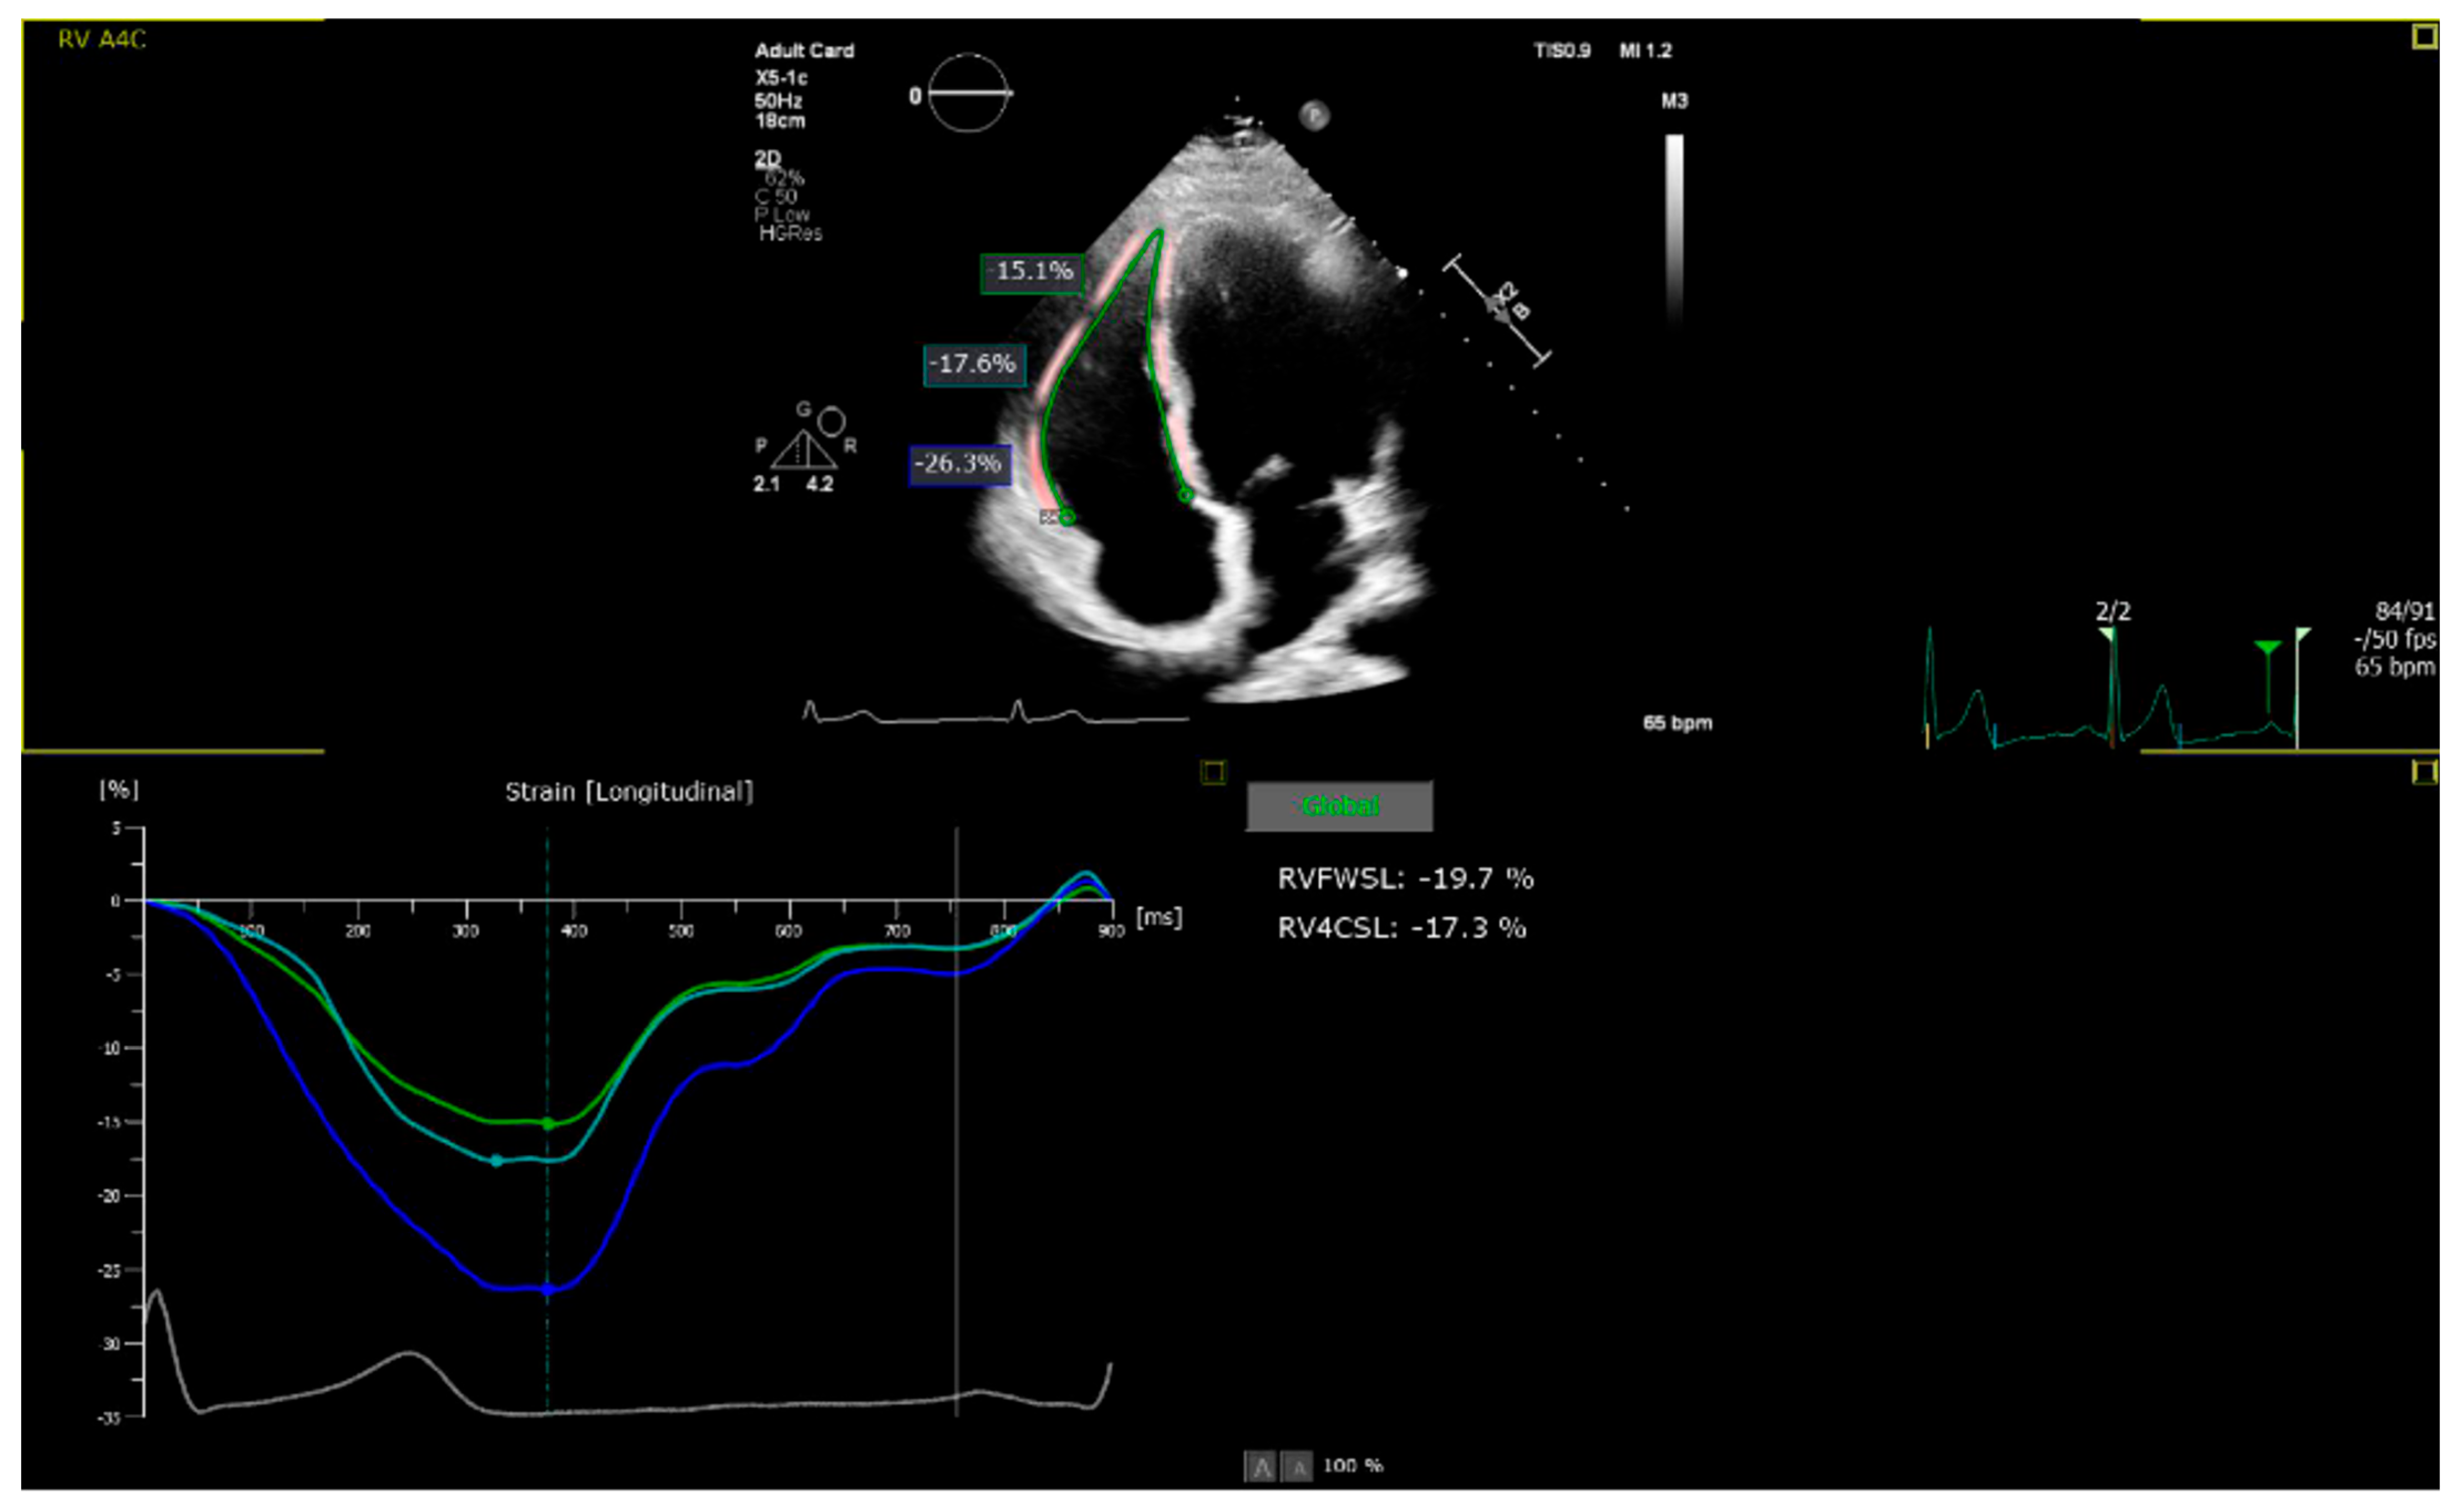

All images were acquired in the focused (on the RV) apical four-chamber view and exported digitally (Figure 2). Subsequently, the parameters 2D RVFWLS and 2D RV4CLS were analyzed using AutoStrain RV 5.0 (Philips, Eindhoven, The Netherlands), which automatically generated RV strain curves and evaluated the 2D RVFWLS parameter as the average value of these curves at the basal, mid-ventricular, and apical segments. For each patient, the analysis was performed across different cardiac cycles from the same cine loops, when accessible, and the results were averaged. The right ventricular (RV) strain was measured as endomyocardial strain using a six-segment model and is referred to in the text as an absolute value. A frame rate of clips used for analysis, including global longitudinal strain, was 60 frames per second, in accordance with recent guidelines [20].

RV functional parameters also showed a graded impairment across BMI categories. RV free wall longitudinal strain (RVFWLS) declined from −27.6 ± 4.0% in normal weight to −22.9 ± 4.4% in overweight and −19.1 ± 5.0% in obese individuals. Similarly, RV four-chamber longitudinal strain (RV4CLS) decreased stepwise (−23.3 ± 3.6%, −20.3 ± 3.5%, and −16.5 ± 3.8%, respectively; both p-trend < 0.001). These graded differences are illustrated in Figure 2 and Figure 3.

Figure 2. Apical right ventricular—focused four-chamber view obtained by two-dimensional echocardiographic acquisitions and automatic analysis of the right ventricular strain using two-dimensional speckle transthoracic echocardiography (authors).